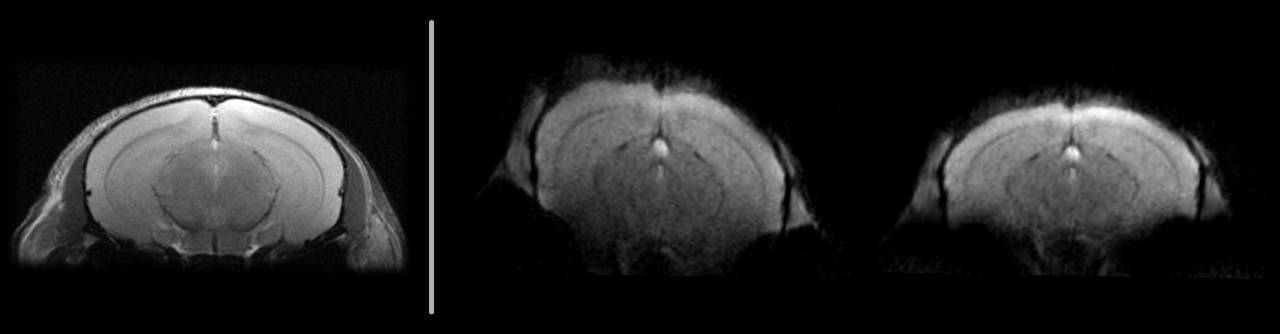

B0 Distortion Correction for EPI

• ⁠Robust field map-based correction of geometric distortions

• Improved anatomical accuracy for key applications, e.g. fMRI and DTI

• Integration into the standard reconstruction pipeline

Single-shot EPI of in vivo mouse brain at 7T: original (middle) and field map-based corrected (right). Anatomical RARE reference (left).